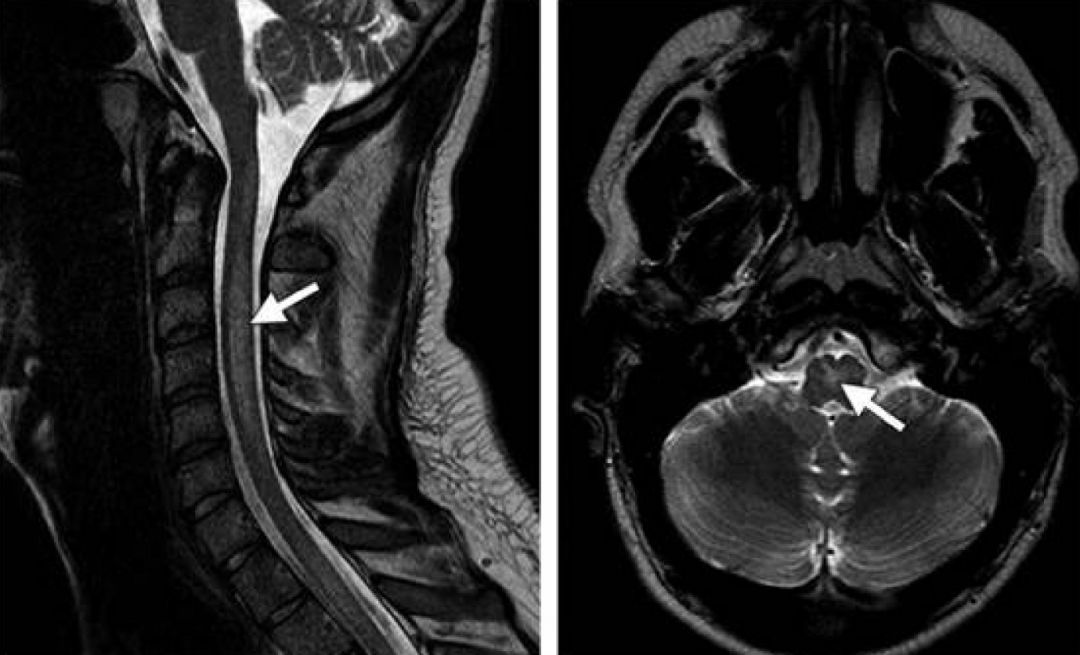

男性患者,23岁,牙科术后急起手足麻木刺痛。Lhermitte sign阳性。

答案:笑气中毒。

笑气中毒现在大多数都可以想到,首先这样的患者在增多,有的老师一个门诊可以见到2-3个笑气中毒,其次,本病例在医脉神经的普及下变得too simple。笑气,即一氧化二氮(N2O)是一种无色有甜味的气体,中枢神经系统主要作用于N-甲基-D-天冬氨酸(NMDA)阿片受体并间接抑制T型钙离子通道,产生麻醉和镇痛作用,早期常被用于牙科手术的麻醉和止痛。吸入N2O可以抑制内啡肽的释放,产生短暂的愉悦体验,使人发笑,俗称“笑气”。

N2O滥用的毒性作用主要分为神经损害症状和精神症状,神经损害如脊髓病、周围神经病、亚急性联合变性;精神症状如情绪变化、谵妄、精神错乱和认知功能障碍,其中以神经损害为表现者占多数,以颈胸段脊髓后索病变为甚。毒性主要因其不可逆的结合维生素的钴原子,导致B12的氧化失活。长期滥用或短时间内大量吸入N2O可导致和维生素B12缺乏类似的神经损害(运动纤维和感觉纤维多同时受累,运动轴索更易受损);MRI可见脊髓横断面倒V形高信号影。治疗上首先是停止接触N2O,补充足量的维生素B12,补充蛋氨酸、叶酸等作为辅助治疗。